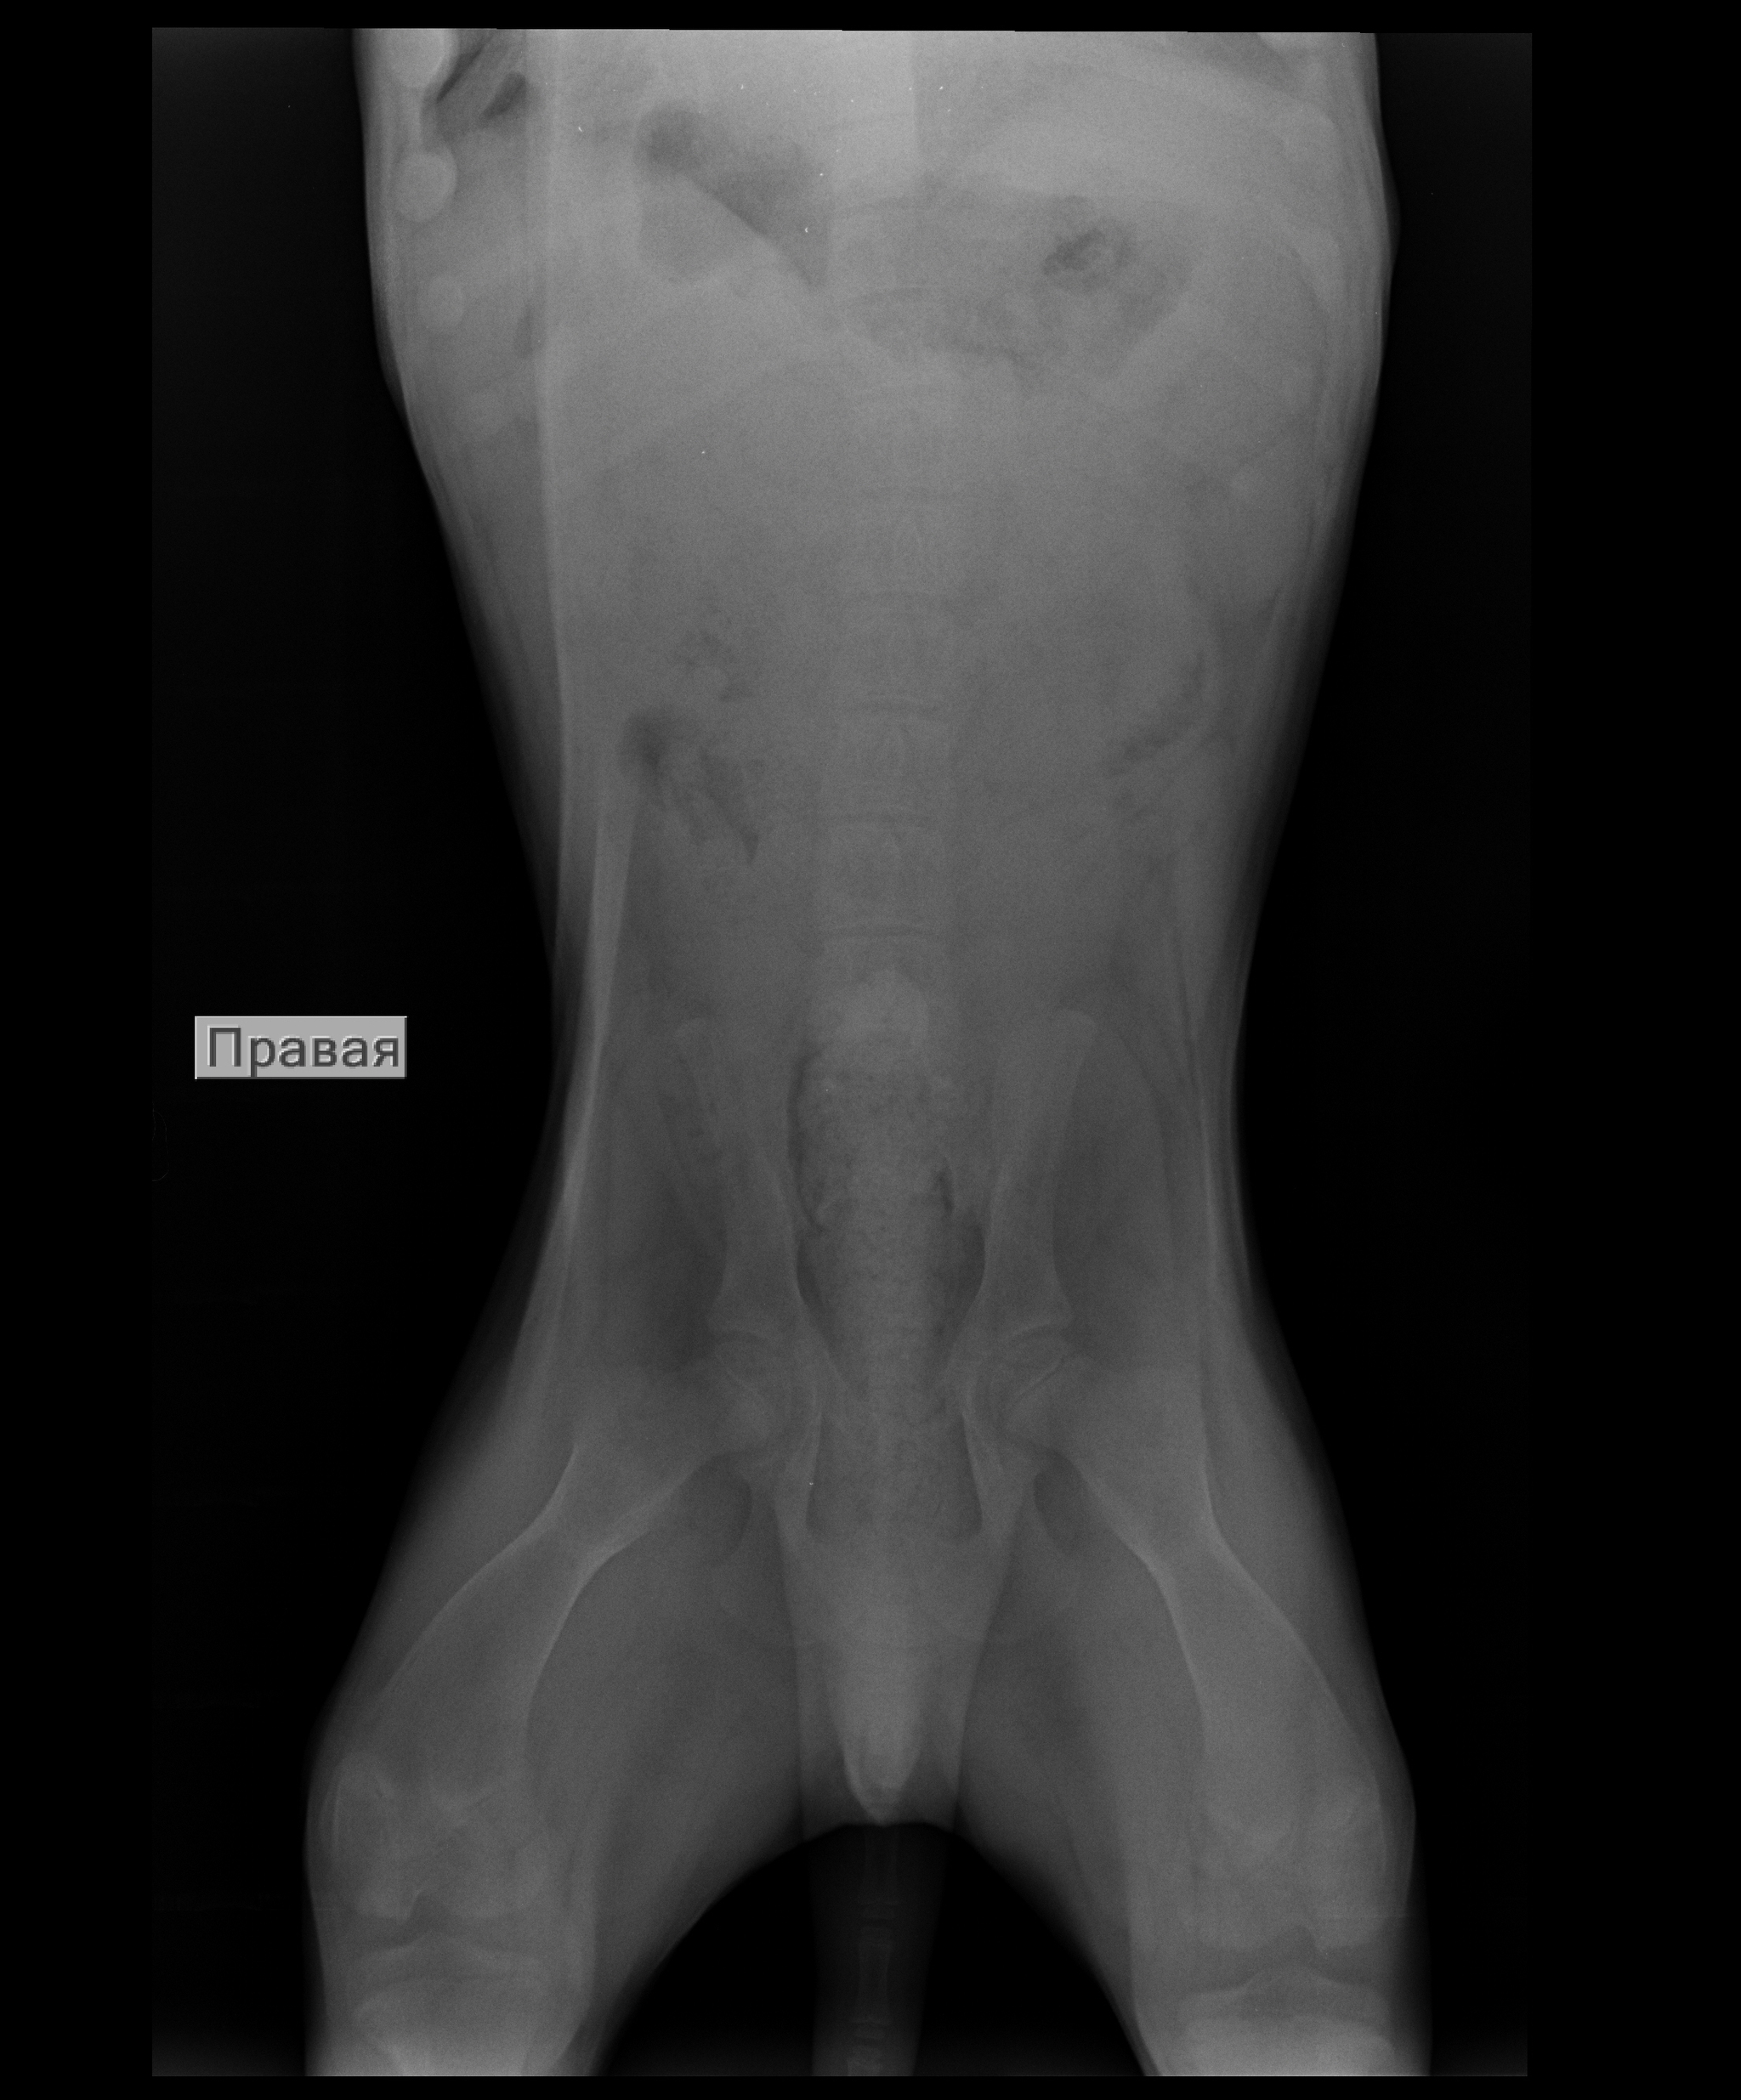

Выше представлены рентгенографические снимки котенка, которого ранее кормили кашей и мясом, а затем перевели на промышленные корма. Разница в 5 месяцев. Может показаться, что изменилось качество снимка за счет смены аппарата, например, или фотошопа :), но нет. На втором снимке заметно выше плотность кости.